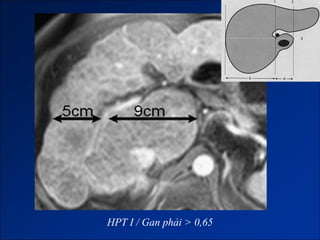

Figure 1. Transverse contrast material-enhanced gradient-echo MR image (120/2.3, 90° flip angle)

shows method of obtaining the C/RL.

©2002 by Radiological Society of North America   Awaya H et al. Radiology 2002;224:769-774

HPT I / Gan trái < 0,35

HPT I / Gan phải > 0,65

Figure 1. Transversecontrast material-enhanced gradient-echo MR image (120/2.3, 90° flip angle) shows method of obtaining the C/RL. ©2002 by Radiological Society of North America Awaya H et al. Radiology 2002;224:769-774

HPT I /Gan trái < 0,35

HPT I /Gan phải > 0,65

• #67 Figure 1. Transverse contrast material-enhanced gradient-echo MR image (120/2.3, 90° flip angle) shows method of obtaining the C/RL. Line 1 is drawn through the right lateral wall of the bifurcation of the main portal vein and parallel to the midsagittal plane of the body. Line 2 is drawn through the most medial margin of the caudate lobe and parallel to line 1. Line 3 is drawn perpendicular to lines 1 and 2 and midway between the main portal vein and inferior vena cava. Line 1′ is drawn through the right lateral wall of the bifurcation of the right portal vein rather than the bifurcation of the main portal vein. Distance C is the width of the caudate lobe measured by using the main portal vein. Distance R is the width of the right lobe measured by using the main portal vein. The ratio of C to R is the C/RL-m. Distance C′ is the width of the caudate lobe measured by using the right portal vein. Distance R′ is the width of right lobe measured by using the right portal vein. The ratio of C′ to R′ is the C/RL-r.